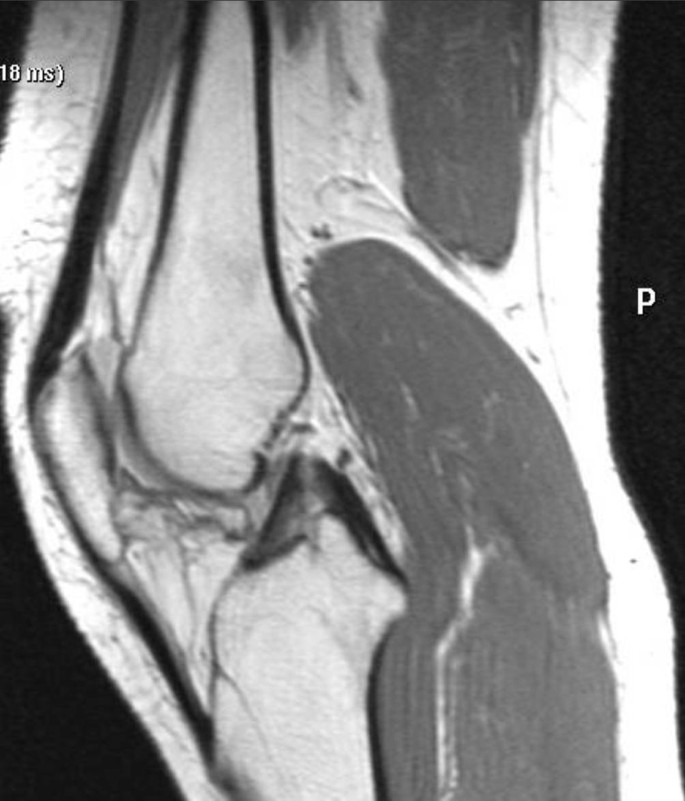

Durch die Entnahme aus dem Streckbandapparat kann es zu einer Schwächung der Extensionskraft und somit der Quadrizepsmuskulatur kommen. Besteht zusätzlich eine ausgeprägte Fibrose der Patellasehne mit Verkürzung, führt dies zu einem Tiefstand der Patella (Patella baja; [16]). Dies wird Patella-Inferior-Syndrom genannt (Abb. 12).

Abb. 12

figure 12

In der sagittalen T1-Sequenz sind Irregularitäten der Patellasehne nach Patellasehnenentnahme und ein Tiefstand der Patella durch Kontraktion der Patellasehne und Schwächung der Quadrizepssehne erkennbar (Patella-Inferior-Syndrom)